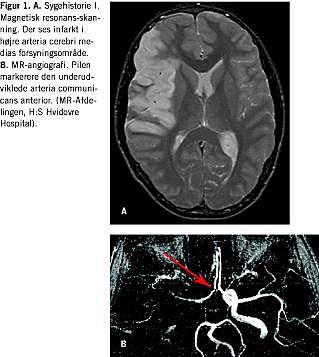

På grund af progredierende symptomer foretog man magnetisk resonans (MR)-skanning af cerebrum, og ved skanningen kunne man påvise iskæmiforandringer i højre hemisfære svarende til a. cerebri medias forsyningsområde. Ved angiografi sås der intet flow i højre a. carotis interna og kun sparsomt flow i højre a. cerebri media og enkelte af dennes forgreninger. Circulus Willisii (circulus arteriosus cerebri) fandtes inkomplet med en underudviklet a. communicans anterior (Figur 1 ).